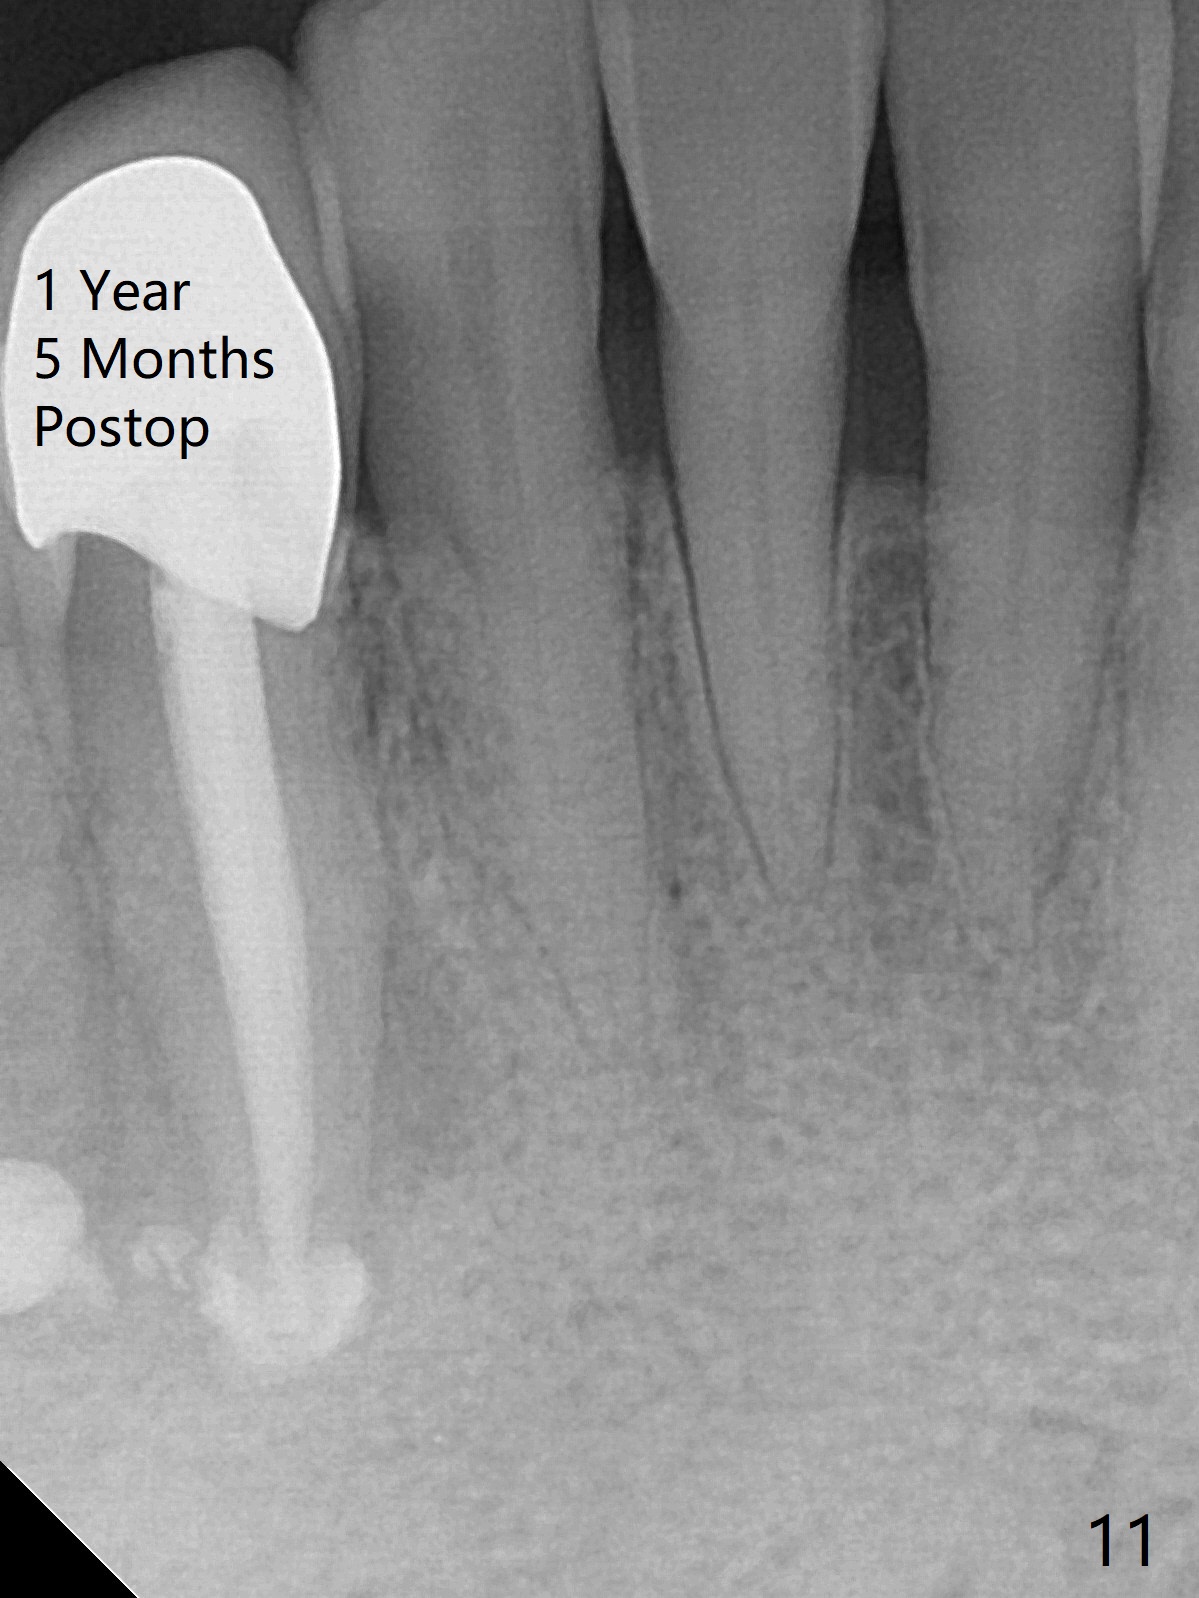

The patient reports that the fistula disappears after initial RCT at #27, but it seems to re-appear 1 month post canal debridement (Fig.5 >). After repeated debridement with #40 hand file at 23 mm, apply Endo Sequence BioCeramic Sealer and insert GT 40/.08 master cone with black carrier (Fig.6). One hour later, the patient returns with re-appearance of the fistula (Fig.7). Following local anesthesia, poking the fistula leads to sealer escape (Fig.8). After debridement of the fistula until the bone, PA is retaken (Fig.9). A crown was made in China; mesial radiolucency starts (Fig.10). The tooth remains asymptomatic 1 year 5 months postop (Fig.11). There is a lingual fistula with enlarged mesial radiolucency 2 years 3 months postop (Fig.12-14).